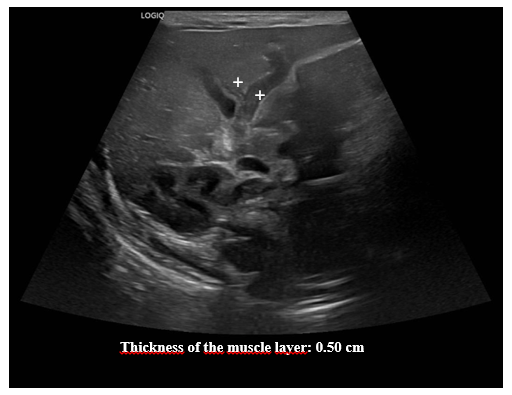

Ultrasound of the abdomen. The liver, gallbladder, bile ducts, pancreas, spleen, right and left kidneys, bladder, and retroperitoneum are normal. Additional examination focusing on the pylorus reveals a pyloric canal diameter of 20 mm, a muscle layer thickness of up to 5 mm, and an anteroposterior diameter of the pyloric canal of 16.4 mm.

Conclusion: Ultrasound findings suggestive of developing pyloric hypertrophy, to be correlated with current clinical presentation (Figures 1–3).

Figure 3 Pylorus ultrasound. Measuring the thickness of the muscle layer.

Ultrasound images of the pylorus show a thickness of the muscle layer of 0.50 cm.

Ultrasound is the test of choice for the diagnosis of HPS. There are ultrasound parameters that allow the diagnosis of this entity to be made. Among these are the length of the pylorus, the muscle thickness and the diameter of the pylorus. However, there are variations in the measurements of these parameters. Piotto et al.,5 report studies where the measurements of these parameters vary, with pylorus length between 14-20 mm, muscle thickness between 2.5-4.8 mm, and pylorus diameter between 10-25 mm. In their study, Piotto et al.,5 found among 321 neonates without HPS an average length of 2.8 mm, standard deviation (SD) 0.6 mm; muscle thickness of 1.3 mm, SD 0.3 mm; and pylorus diameter of 8.2 mm, SD 1.1 mm. Among 286 neonates with HPS, the mean length was 16.3 mm, SD 2.3 mm, muscle thickness 2.9 mm, SD 0.5 mm, and pyloric diameter 38.4 mm, SD 18.5 mm. The ultrasound findings of our patient identified a diameter of the pyloric canal of 20 mm, a thickness of the muscle layer of up to 5 mm, and an anteroposterior diameter of the pyloric canal of 16.4 mm, all above normal values.